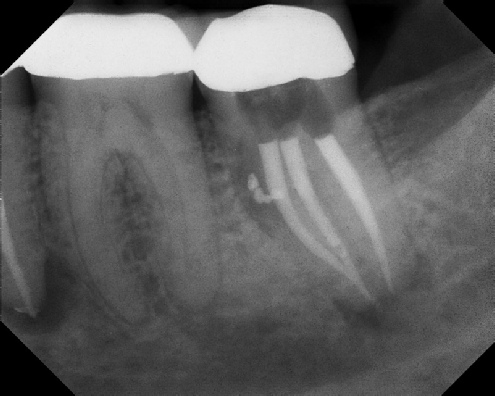

Root Canal Retreatment - Meriden 8 mos. recall Post-op Pre-op